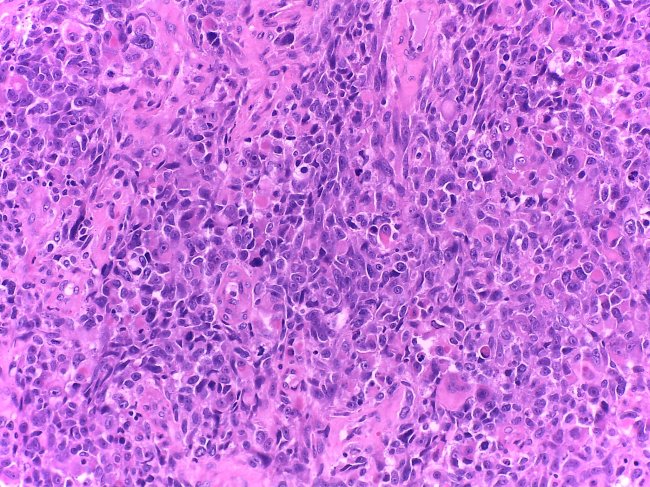

• Anatomia Patológica